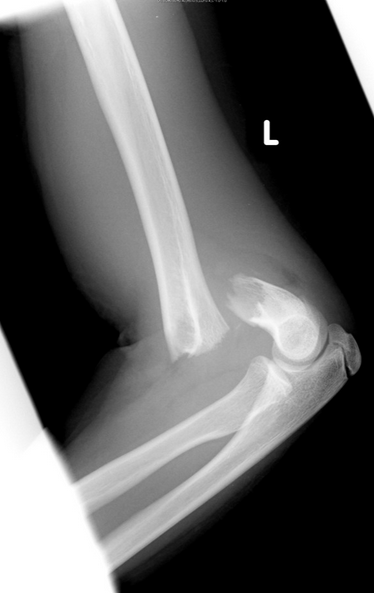

A 44 year old male presents to the ED after getting in a gang fight. He says he was hit just above the elbow with a baseball bat. His x-ray is shown below. What motor tests could you do to assess if nerve damage has also occurred?

The median nerve is subject to injury in this case. You could test thumb abduction, extension and opposition. You could also test wrist flexion and flexion of the index and middle fingers. You should also test for sensory deficit in the distribution of the median nerve.